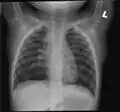

-

Chest radiograph demonstrates thickening and dilatation of the bronchioles